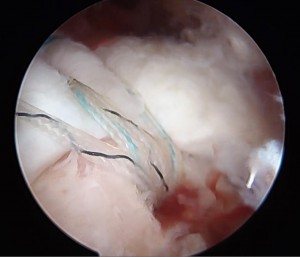

腱板が剥がれ穴があいています。下に見えるのは骨です。

2 骨にアンカー(糸のついたビスのようなもの)をうち腱板に糸を通しているところ

3 腱板に通した糸を骨に固定して終了です。